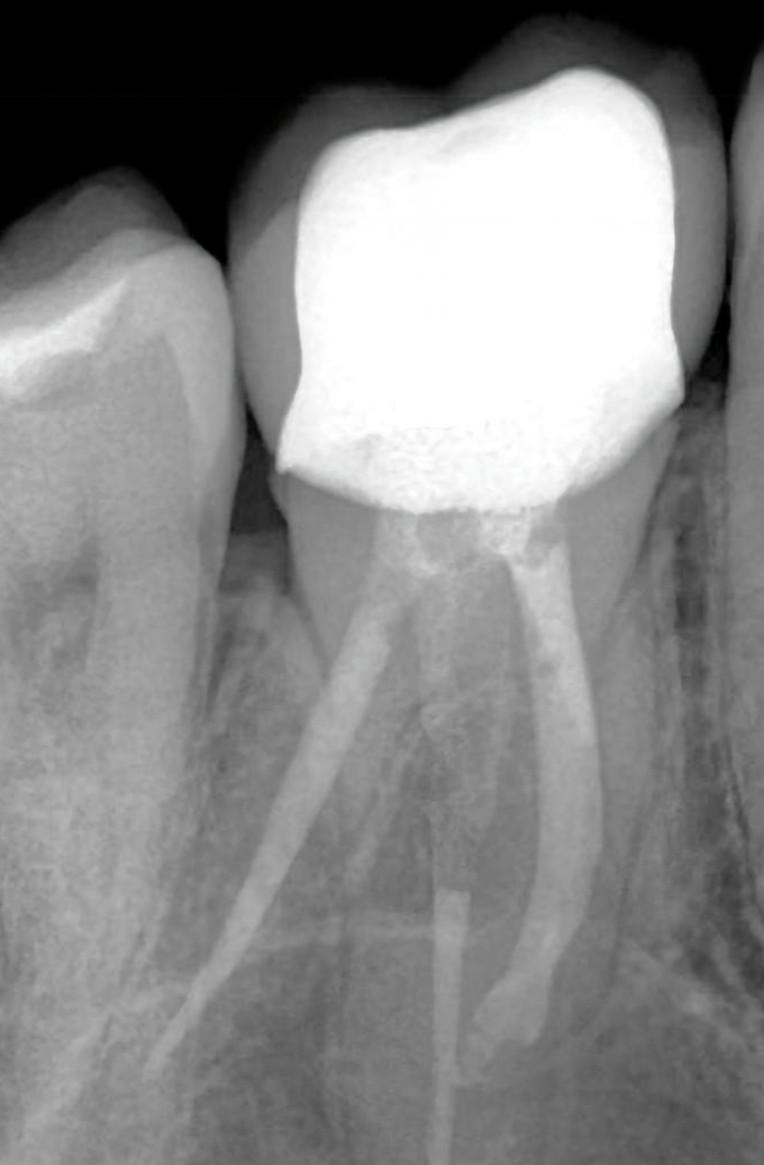

После установки коронки в межз.пространства стала забиваться пища и воспаляться десна.Также она не совпадала по цвету. Ортопед заверил что конструкция точно без зазоров и нависаний прилегает к зубу.(сн.1)